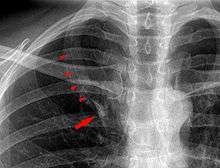

In human anatomy, an azygos lobe is a congenital variation of the upper lobe of the right lung.It is seen in 1% of the population. Embryologically, it arises from an anomalous lateral course of the azygos vein in a pleural septum within the apical segment of the right upper lobe or in other words an azygos lobe is formed when the right posterior cardinal vein, one of the precursors of the azygos vein, fails to migrate over the apex of the lung and penetrates it instead, carrying along two pleural layers that invaginates into the upper portion of the right upper lobe . As it has no bronchi, veins and arteries of its own or corresponding alteration in the segmental architecture of the lung, so it is not a true (misnomer), or even accessory, pulmonary lobe, but rather an anatomically separated part of the upper lobe. It is usually an incidental finding on chest x-ray or computed tomography and is as such not associated with any morbidity but can cause technical problems in thoracoscopic procedures .